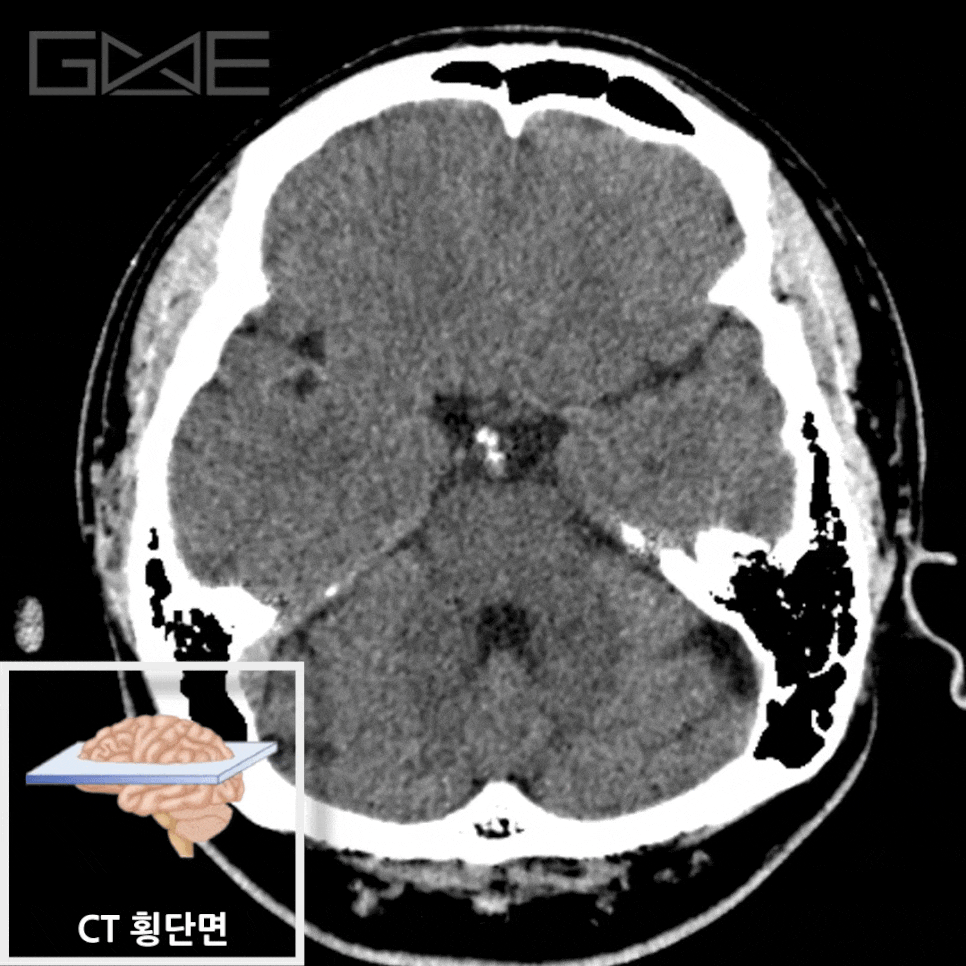

뇌CT

급성 뇌출혈·외상·응급 신경학적 이상 평가에 빠르고 유용한 단층 X선 검사입니다.

하지만, 뇌검사를 할 때, 뇌CT 검사가 이뤄지는 경우는 극히 드뭅니다.

그 이유는 뇌CT는 빠르게 뇌의 구조적 이상을 확인할 수 있는 검사로, 응급 상황에서 특히 유용합니다.